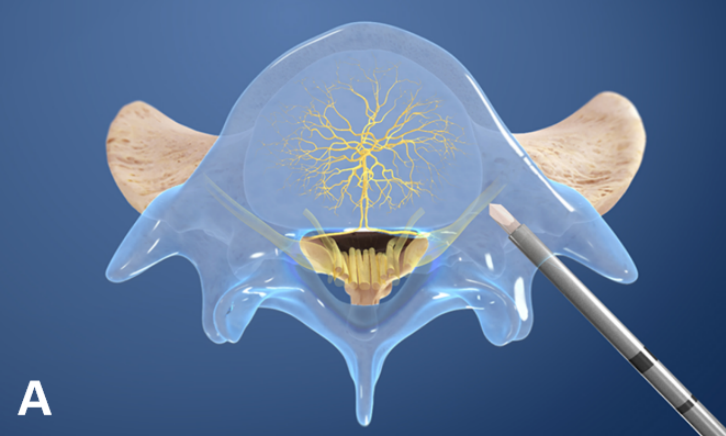

②椎体内椎基神经射频消融术

③经皮内镜下硬膜外椎基神经激光消融术

值得关注的是,系列前瞻性多中心随机对照研究和前瞻性观察研究证实椎体内椎基神经射频消融术可有效缓解疼痛性 Ⅰ 型或 Ⅱ 型 Modic 改变患者的腰痛症状,减少阿片类药物的用量,且疗效优于保守治疗。

国际脊柱外科手术学会指南也推荐采用椎体内椎基神经射频消融术治疗 Ⅰ 型或 Ⅱ 型 Modic 改变引起的慢性腰痛。

2021 年,Conger 等进行系统综述发现有中等质量的证据表明,在根据存在 Ⅰ 型或 Ⅱ 型 Modic 改变选择慢性腰痛患者时,椎体内椎基神经射频消融术可有效改善慢性腰痛患者的疼痛和功能障碍。这可能与灭活了椎体内的椎基神经, 阻断了神经传导通路有关。